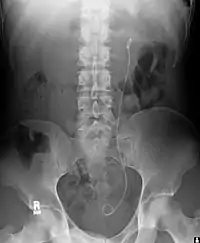

يتم استخدام الحال الدعامي لضمان سالكية الحالب، الذي قد يؤثر سلبا، على سبيل المثال، التي تكون حصوات الكلى. ويستخدم هذا الأسلوب في بعض الأحيان، كإجراء مؤقت، لمنع تلف الكلى، حتي يتم القيام بازاله الحصو. يشار مرات سكنى 12 شهرا أو أكثر لعقد الحالب مفتوح، والتي يتم ضغطها بواسطة الأورام في حي من الحالب أو أورام الحالب نفسها. في كثير من الحالات هذه الأورام هي غير صالحة للعمل ويتم استخدام الدعامات لضمان تصريف البول من خلال الحالب. وإذا خطر الصرف لفترات أطول يمكن أن تتلف الكلى. المضاعفات الرئيسية مع الدعامات الحالب والتفكك، والعدوى والحصار من قبل القشرة. وقد وافق مؤخرا الدعامات مع الطلاء (مثل الهيبارين) للحد من العدوى، وبالتالي تجلب التبادلات الدعامة.